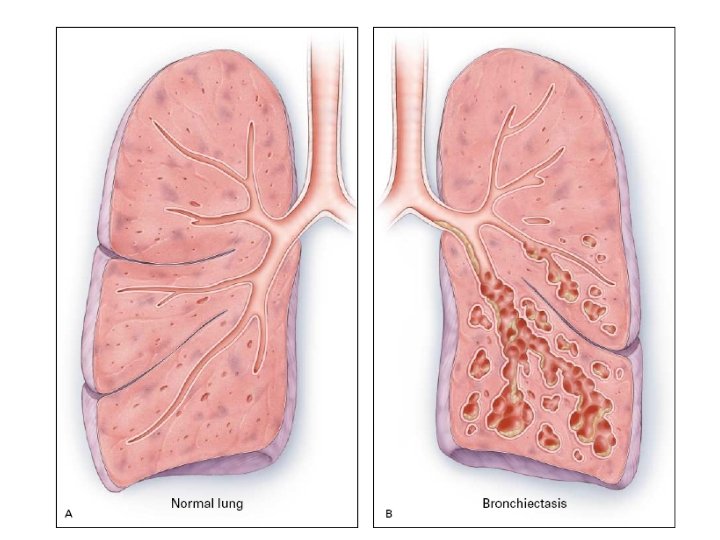

BRONCHIECTASIS • • • Definition: Abnormal and permanent dilation of bronchi. Focal or diffuse distribution It is a disorder that typically affects older individuals approximately 2/3 of patients are women It is usually acquired but may result from an underlying genetic or congenital defect of airway defences Clinical consequences – • chronic and recurrent infection and • Pooling of secretions in dilated airways.

Clinical features of bronchiectasis Due to accumulation of pus in dilated bronchi • Chronic productive cough usually worse in mornings and often brought on by changes of posture. • Sputum often copious and persistently purulent in advanced disease. • Halitosis is a common accompanying feature • SOB

Clinical features of bronchiectasis con… • Bronchiactasis may involve any part of the lungs but the more efficient drainage by gravity of the upper lobes usually produces less serious symptomes & complications than when bronchiactasis involves the lower lobes.